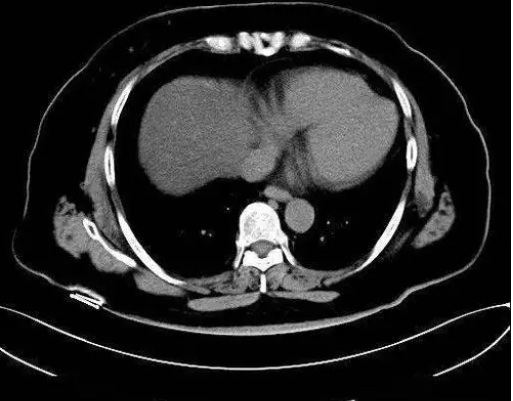

- 形态变异:獭尾肝是肝脏结构的一种变异,表现为肝左叶向左后方凸起,形似水獭的尾巴。

- 常见性:獭尾肝在部分正常发育的肝脏以及合并有脂肪肝的情况下较为常见。

- 与脾脏疾病的鉴别:由于獭尾肝的形态特殊,有时可能会被误诊为脾肿大、脾肿瘤等脾脏疾病。因此,在临床上需要进行仔细的鉴别诊断。